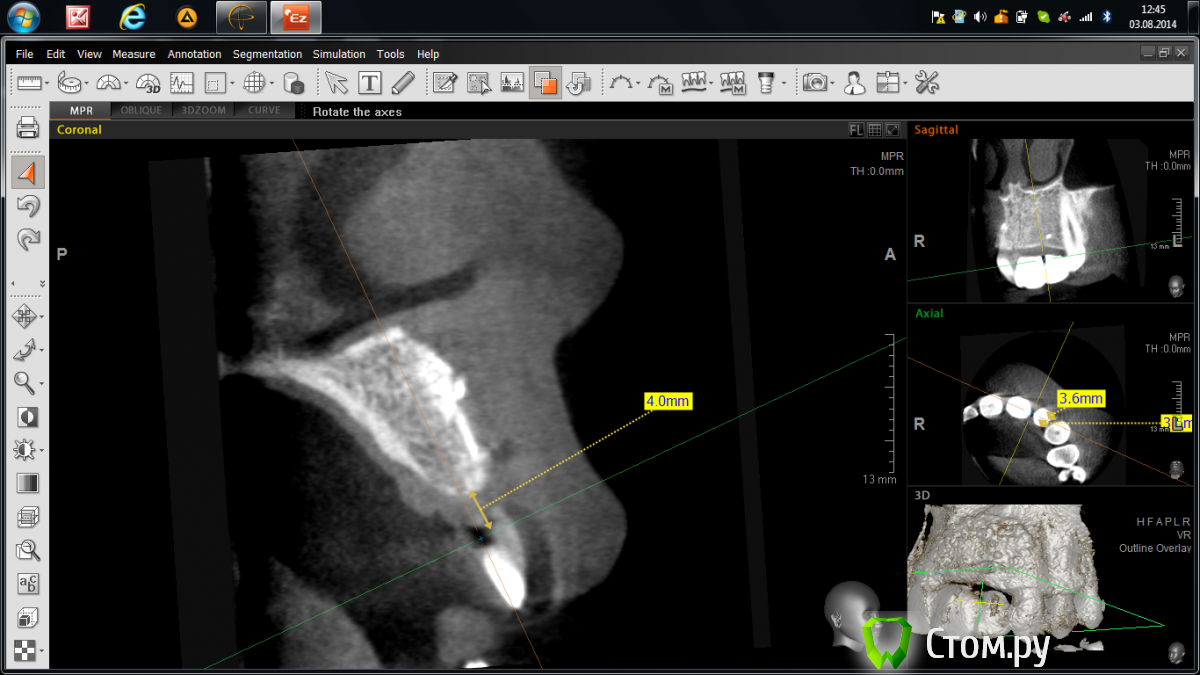

Abuk Опубликовано 3 августа, 2014 Поделиться Опубликовано 3 августа, 2014 Добрый день,коллеги.Горит,помогайте! Года 2 назад,когда я был молод,красив и малоопытен)),консультировал пациентку,на предмет восстановления имплантатами двух отсутствующих зубов:2.1,2.2; на месте которых висел композитный пртез. Отрофия кости была заметна невооруженным глазом,КТ подтвердило. Начинали с 3D пластики.Старые фото, пока, не нахожу((( Ширина кости была около 3 мм по 11-13 мм гребню.После операции ,спустя 4 месяца,пациентка ушла в декрет и пропала на 2 года.Ныне сделав рентген - шаблон,отправил на КТ(.Ошибки я учел,по поводу костной пластики).Недостаток в верхушке гребня и воостановление десневого сосочка-задачи,которые предстоит решить.Посоветуйте:возможно ли1.без повторной агрессивной костной пластики2.или можно ограничиться только работой с мягкими тканями???????? Ссылка на комментарий

Mane Опубликовано 3 августа, 2014 Поделиться Опубликовано 3 августа, 2014 Устанавливайте два тонких имплантата размером до 3,5 мм в диаметре. Если проходят по канонам.Сразу естесственно с расщеплением и направленной костной регенерацией и десневой аугментацией. Задача не топить платформу импланта в кость. Установить имплант в уповень с костью. И далее вторым этапом через 6 мес открытие имплантов с пластикой сосочков. Возможно повторная десневая аугментация. 2 Ссылка на комментарий